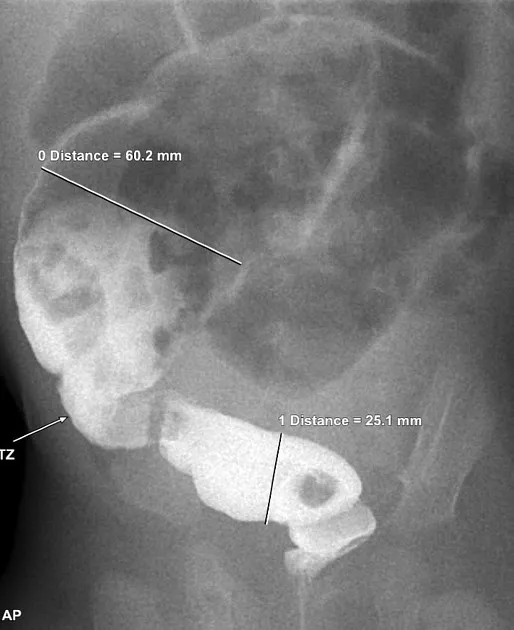

- Contrast Enema (Barium/water-soluble): Crucial for identifying the transition zone (narrowed aganglionic segment, dilated ganglionic proximal colon). Retention of contrast > 24 hours is highly suggestive.

- 📌 "Transition Zone = Trouble Zone"

- Barium enema often shows a transition zone between a narrowed aganglionic segment and a dilated proximal bowel.